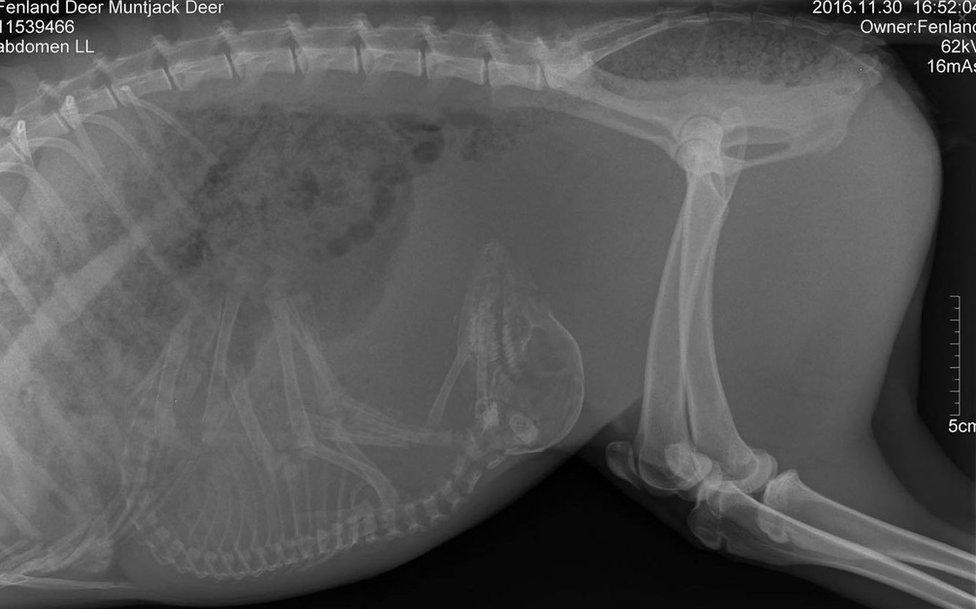

An X-ray unexpectedly showed the female muntjac was expecting

A scan found the animal had suffered lacerations and a dislocated ankle but also that she was heavily pregnant. The centre said on Sunday morning the doe had given birth overnight.